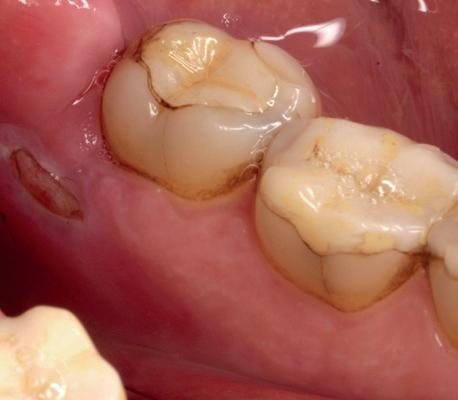

In afbeeldingen 4a-c is het resultaat drie maanden na het plaatsen van het implantaat te zien. De genezing is volledig en de verwijzer kan de suprastructuur vervaardigen (afbeelding 4a-4c).

In afbeeldingen 5a-d is de implantaatkroon 37 te zien, twee jaar na plaatsing. Op de röntgenfoto is herstel van zowel corticaal als spongieus bot te zien. (De CB-CT was vervaardigd in verband met implantologische indicatie in het naastliggende gebied).